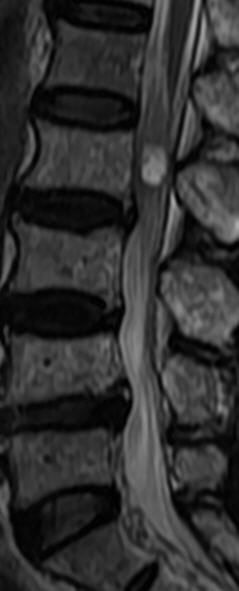

MRI

可提供腰椎管的矢状面、冠状面和轴位横断面上的影像。椎管狭窄以T2加权像显示较好,脑脊液为高信号,产生所谓“脊髓造影”的效果,而骨质增生,骨赘、间盘均为低信号,能清晰地显示椎管狭窄,以及对脊髓的压迫情况。但对肥大的黄韧带、骨质增生等的判断则不如较高清晰度CT扫描。

腰椎正常MRI解剖。

腰椎管狭窄MRI表现。